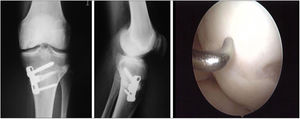

Two patients required special milling of the graft, as the Maxioats® technique did not cover the defect; one received a double graft and, at one year, arthroscopic control of the graft (Figs. 3 and 4); in the other case, the graft was milled by hand, given the defect, and fixed with 2 Herbert screws (Figs. 5 and 6).

Same patient as Fig. 3, at one year, valgus osteotomy and arthroscopic revision.

Same patient as Fig. 5. Result of manually milled graft fixed with Herbert screws.

In the cases we examined a second time by arthroscopy, we observed the survival of the implanted graft, integration of the edges, and the macroscopic appearance of the cartilage surface, using the OAS protocol, which is complementary to the ICRS results (Table 2).